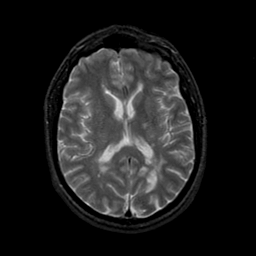

MR Study #23, January 26, 1992 -- Slice #28